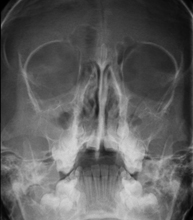

- RX Senos Paranasales

Técnica mediante la cual, utilizando rayos X, se obtienen imágenes de los senos paranasales para su estudio. Indicaciones: dificultad respiratoria nasal, tos crónica, cefalea, mucosidad.